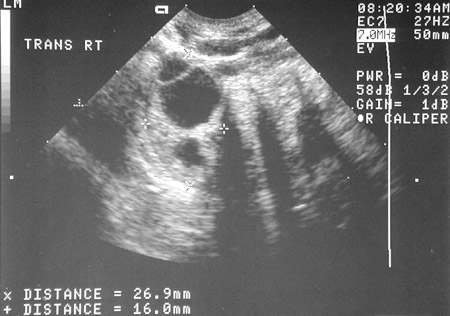

![]() | By transvaginal ultrasound in the view above, a ring-like structure is present in the right adnexal region, highly characteristic for an ectopic pregnancy because no gestational sac was present in the uterine cavity, as seen below, only a thickened endometrium. The beta-HCG was also elevated. |